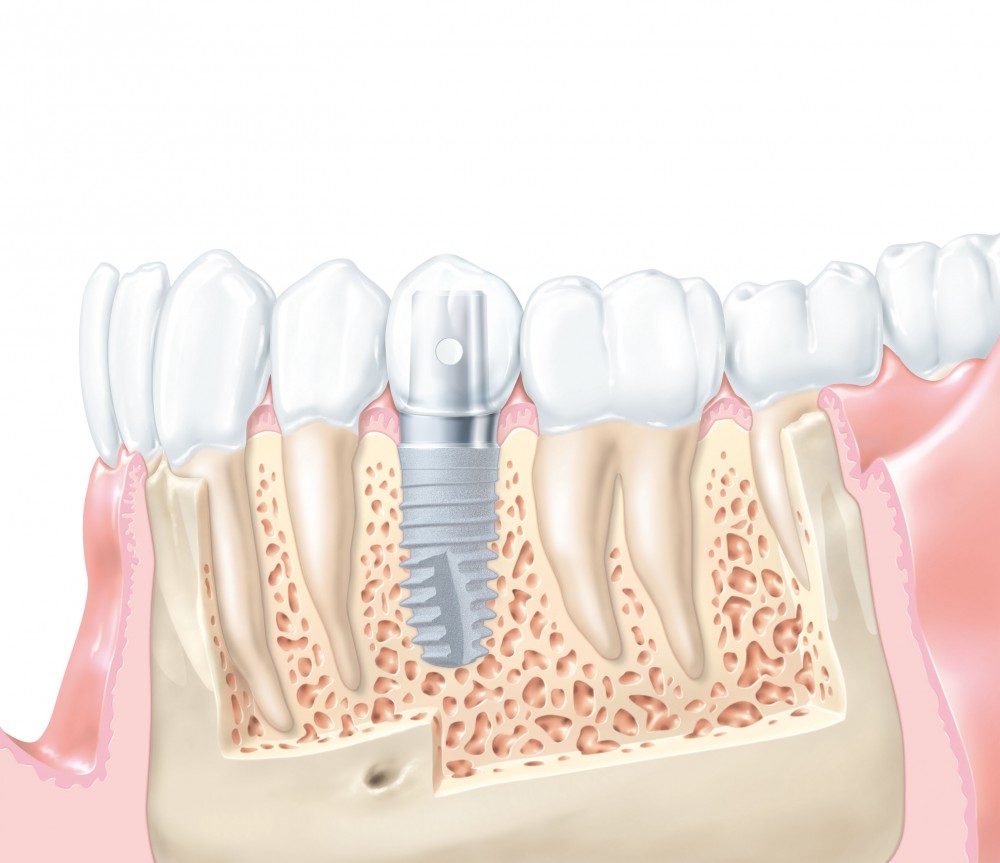

Реплантация зуба: Этапы и особенности операции